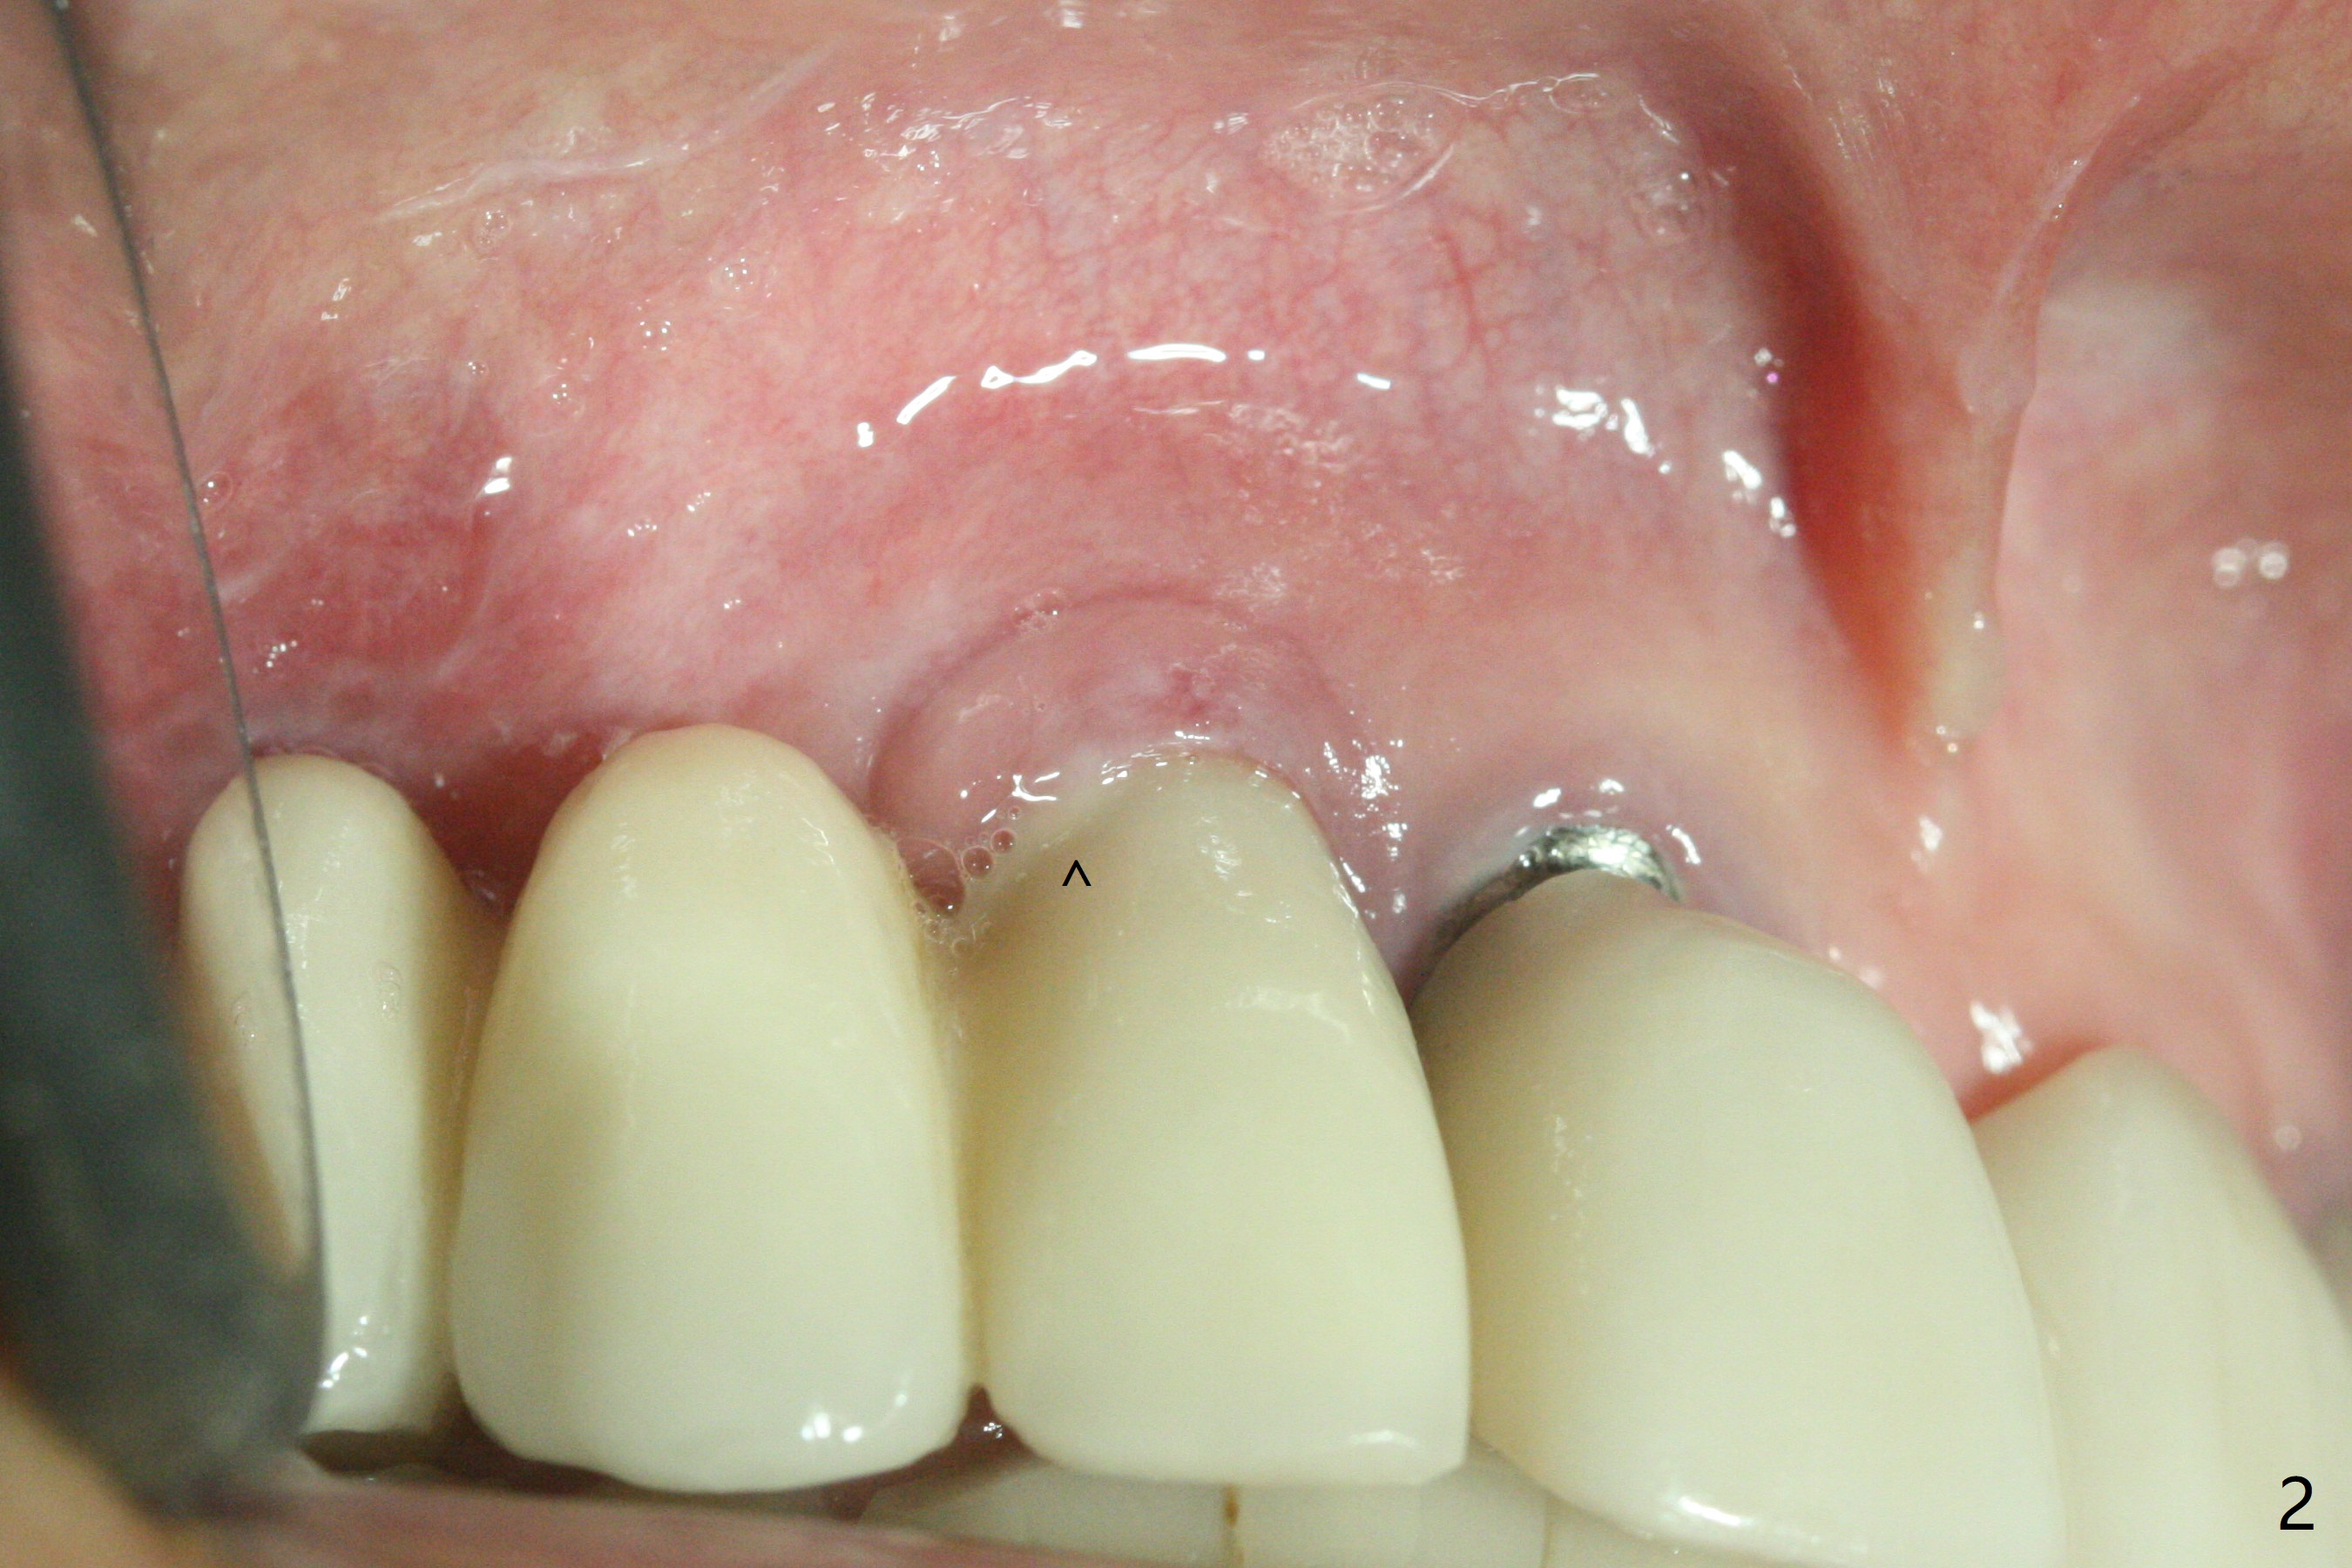

64岁女3-7牙桥,7号牙植体颊侧牙龈缘红肿(图一:*),脓液(图二:^),需要切开清洗,但是6号牙桥墩颊侧非角化龈(N)妨碍切口,所以必须去除桥墩,暴露牙槽嵴顶角化龈(图三:K),容易切开,最后缝合而不容易出血,伤口容易愈合。切开清创后重大发现是牙冠边缘(图四:^)直接接触植体微螺纹,没有基台与牙龈之间形成的屏障,有利于口腔细菌直接感染植体。直感告诉术者必须缩短牙冠边缘,抛光。然后缺损处放置粘性骨粉(图五,八:S,与图七(术前)比较),表面覆盖PRF膜,缝合(图六)。准备术后尽早去除牙冠,预防细菌再次感染。并且在6号牙位植入2x8.5毫米植体。